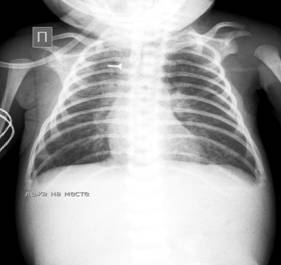

Рентген грудной клетки от 25.09.16-  Атрезия пищевода с нижним трахеопищеводным свищом. (Рис.№2)

25.09.bmp

Рисунок№2